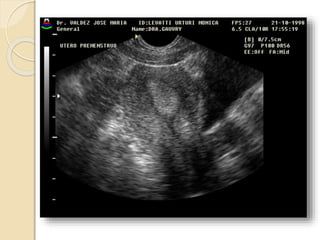

Útero posmenopáusico: Se produce la

atrofia del mismo con disminución de

1 a 2 cm de espesor y 3 a 7 cm de

longitud

Tamaño: Útero posmenopáusico:Se produce la atrofia del mismo con disminución de 1 a 2 cm de espesor y 3 a 7 cm de longitud